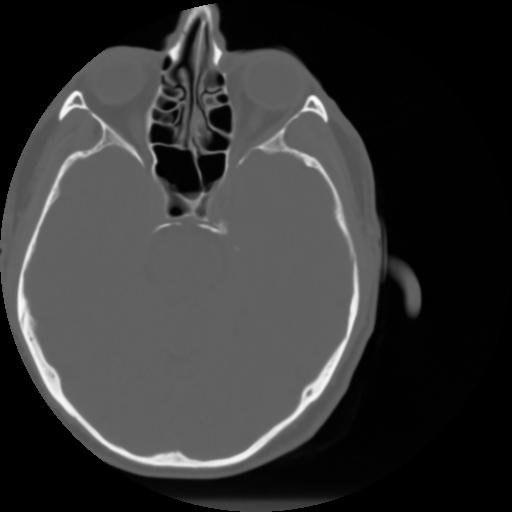

3 CEREBRO,,Axial,3.0,CEREBRO,,